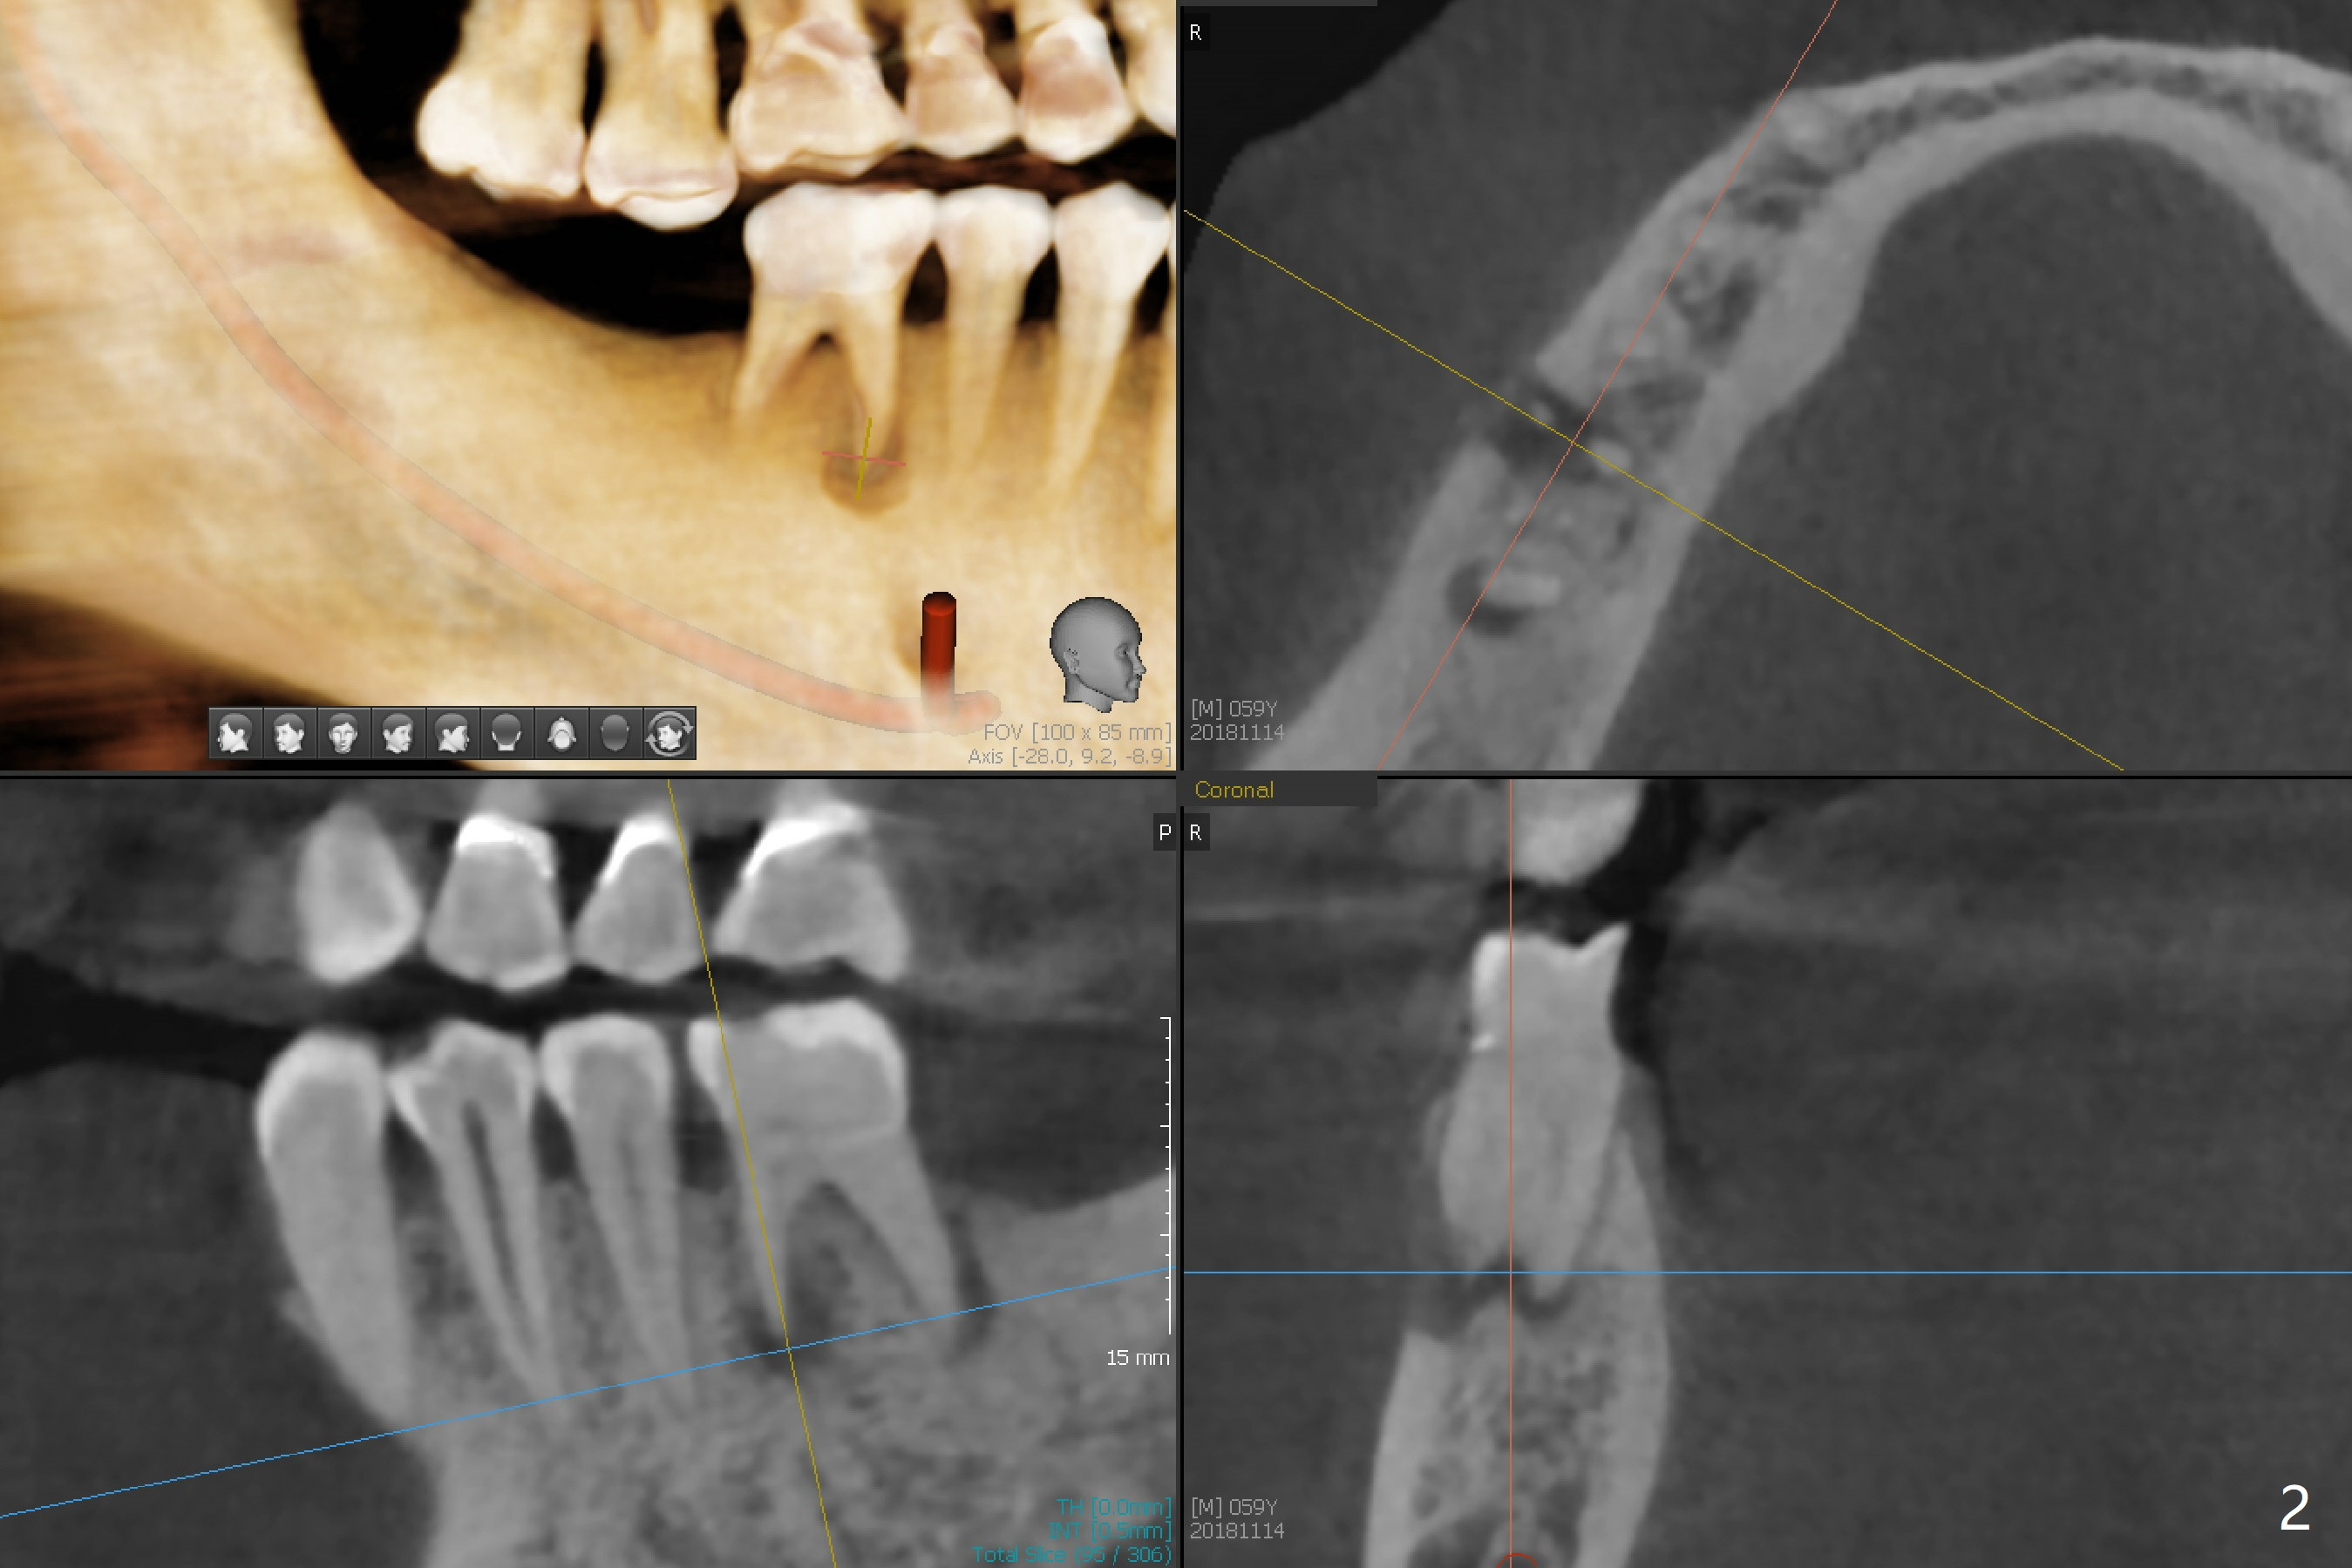

A 59-year-old man has subgingival fracture of the lingual cusps of the tooth #30 (Fig.1) with PARL, especially of the mesial root (Fig.2). An immediate implant will be placed slightly distolingually (Fig.3), while the delayed implant at #31 will be placed in a restorative position (Fig.4). Treat plan orthodontic intrusion of the tooth #2 if the latter is salvageable with periodontal lesion (Fig.1). Keep the tooth #1 in case bands and segmental wire are needed. It will be extracted prior to impression. After extraction, place a bony anchor pin at #31 for #30 osteotomy. When an implant is placed at #30, place a fixture anchor pin and finish osteotomy at #31.